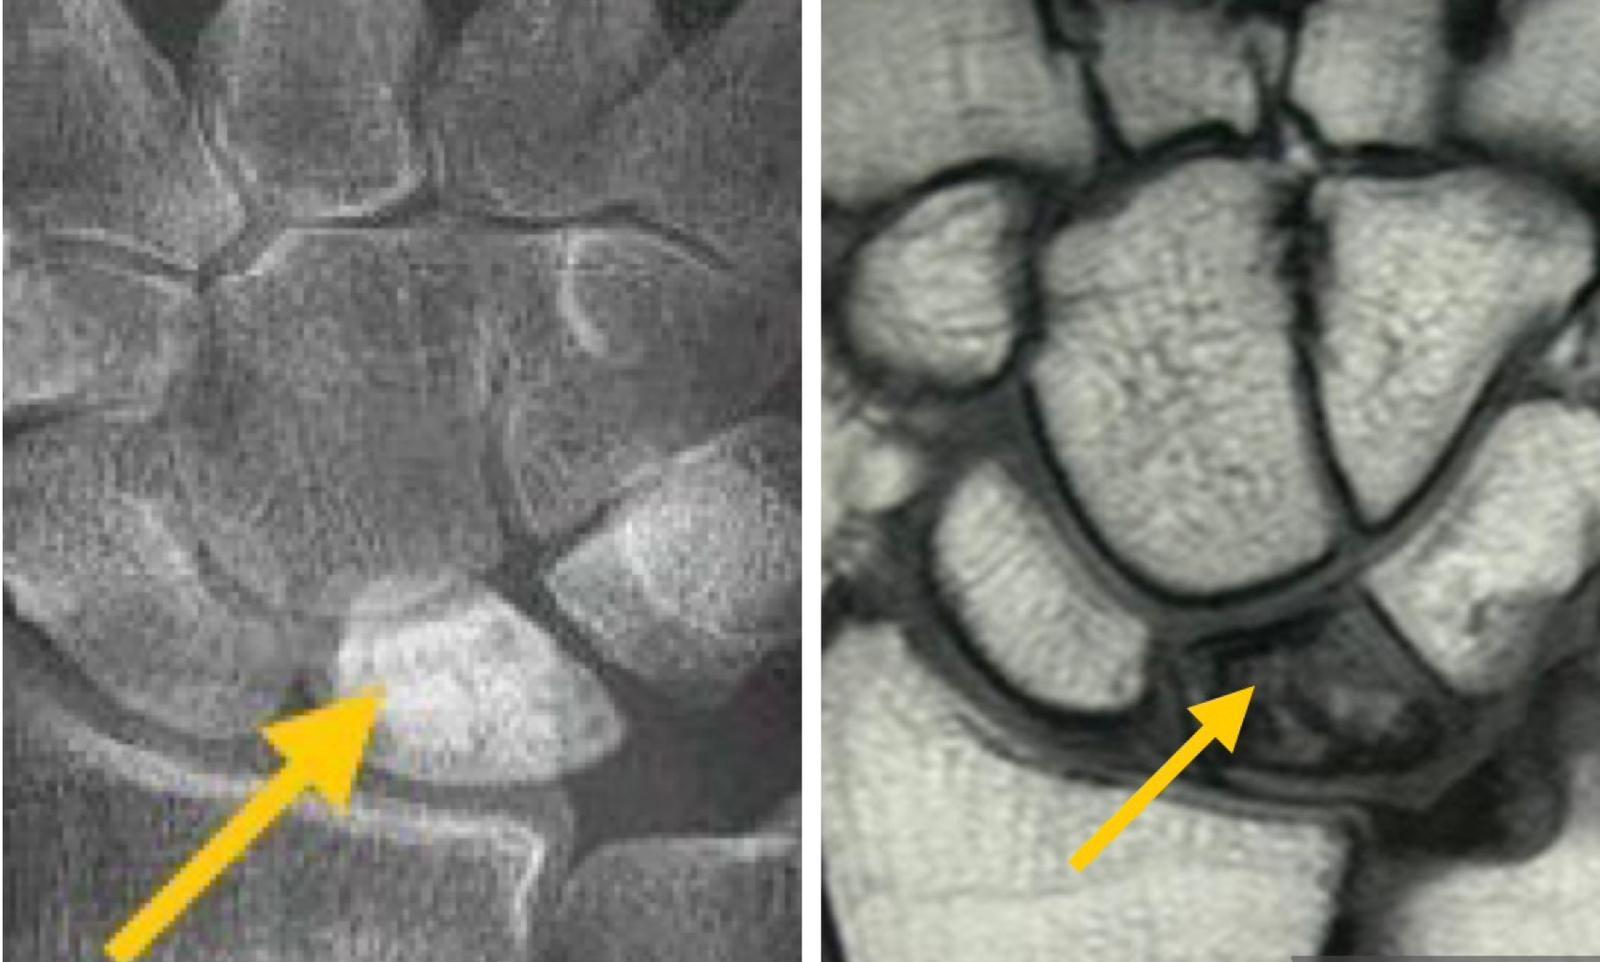

- 第一期:X光大致正常,但在磁力共振(MRI)的T1加權影像中出現低訊號強度(陰),反映月骨缺血令骨髓內脂肪減少;而在T2加權影像中出現高訊號強度(晴),代表骨髓水腫和炎症反應。

- 第二期:X光下月骨的密度會增加(代表骨硬化),較其它腕骨「分外明」,但尚未變形。

- 第三期:X光顯示月骨已經塌陷變形,甚至碎片化;而MRI的T1及T2加權影像皆呈現低訊號強度,證實月骨已壞死並纖維化。